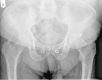

Hyperpharmacotherapy in ageing cystic fibrosis patients: The first report of an atypical hip fracture

Cystic fibrosis (CF) is a common autosomal recessive disorder in Caucasian populations with respiratory, gastrointestinal and endocrine manifestations. Thanks to recent advances in medical therapies and infection control, life expectancy of a patient with CF has significantly increased from less than 5 years in the mid-1900s to almost 50 years nowadays. However, as CF patients are living longer, multimorbidity and Hyperpharmacotherapy are becoming more common. This case illustrates a cascade of problems that ensued from medication side-effects, highlighting the increasing challenge of managing an ageing CF population.